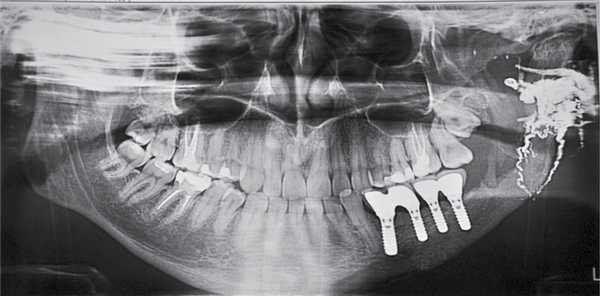

Пациент Н., 21 года, поступил в клинику с диагнозом: АВМ тела и ветви нижней челюсти слева, кровотечение (рис. 1). Рис. 1. Ортопантомограмма пациента Н.: в области тела и ветви нижней челюсти слева определяются области АВМ. Из анамнеза известно, что пациент обратился к стоматологу с жалобами на боль и кровоточивость десны в левой ретромолярной области. Был поставлен диагноз: «перикоронит, ретенция зуба 3.8». При попытке иссечения капюшона слизистой оболочки открылось массивное кровотечение, которое остановили тампонадой. Пациента госпитализировали в ГКБ № 1 Казани. При осмотре в отделении вновь возникло кровотечение, принято решение удалить 3.8 с последующей тампонадой лунки йодоформным тампоном. Кровопотеря во время операции составила 1 л. Пациент санитарной авиацией переведен в Москву. В НМИЦ нейрохирургии им. акад. Н.Н. Бурденко при проведении ангиографии выявлена АВМ тела и ветви нижней челюсти с формированием патологического сосудистого сплетения в крыловидно-небной ямке, крылочелюстном и окологлоточном пространстве. После анализа полученных ангиограмм одномоментно выполнена эмболизация костных полостей АВМ и гипертрофированных патологических ветвей наружной сонной артерии слева препаратом Onyx 18 (рис. 2, 3). Рис. 3. Рентгенограмма пациента Н. после эмболизации полостей и сосудов АВМ ветви нижней челюсти препаратом Onyx 18: прямая и боковая проекции. Рис. 2. Ангиограмма ветвей наружной сонной артерии слева пациента Н. в артериальную и венозную фазу.

Через 6 мес после операции были сняты титановые пластины и выполнена горизонтальная остеотомия сохраненного фрагмента тела нижней челюсти с фиксацией и последующей активацией альвеолярного компрессионно-дистракционного аппарата. Величина дистракции составила 10 мм. Через 5 мес после проведения дистракции и удаления компрессионно-дистракционного аппарата с целью выравнивания уровня края альвеолярного гребня проведена горизонтальная остеотомия костного регенерата, деформация альвеолярного гребня устранена с помощью сэндвич-техники (рис. 5—7). Рис. 6. Остеотомия полученного регенерата и увеличение высоты альвеолярного гребня методом сэндвич-техники. Рис. 7. Ортопантомограмма пациента Н.: реконструкция дефекта нижней челюсти. Рис. 5. Ортопантомограмма пациента Н.: увеличение высоты альвеолярного гребня методом дистракционного остеогенеза.

Через 6 мес после проведения реконструктивно-восстановительных операций по восстановлению высоты и объема нижней челюсти пациенту установили дентальные имплантаты с последующим изготовлением несъемной металлокерамической конструкции. Продолжительность реабилитации пациента после операции по удалению АВМ составила 20 мес (рис. 8). Рис. 8. Ортопантомограмма пациента Н. после установки дентальных имплантатов и изготовления несъемных металлокерамических конструкций. Полная реабилитация.